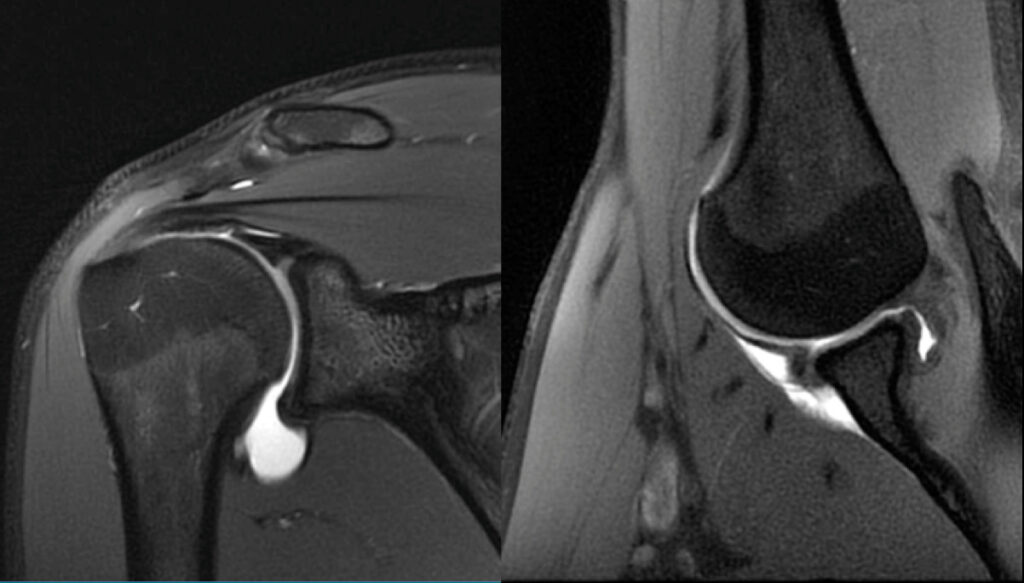

Radiologia muscolo-scheletrica

La radiologia muscolo-scheletrica si focalizza sulla diagnosi e sul trattamento delle patologie ortopediche